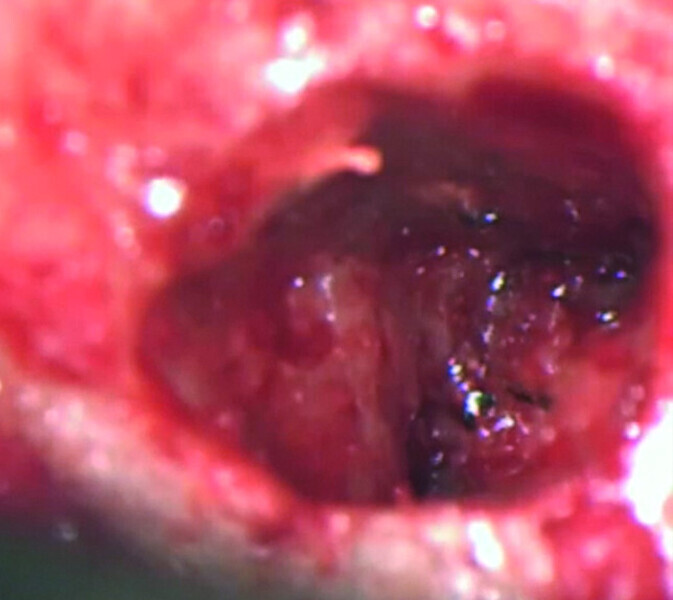

Maxillary sinus and root canal therapy complications